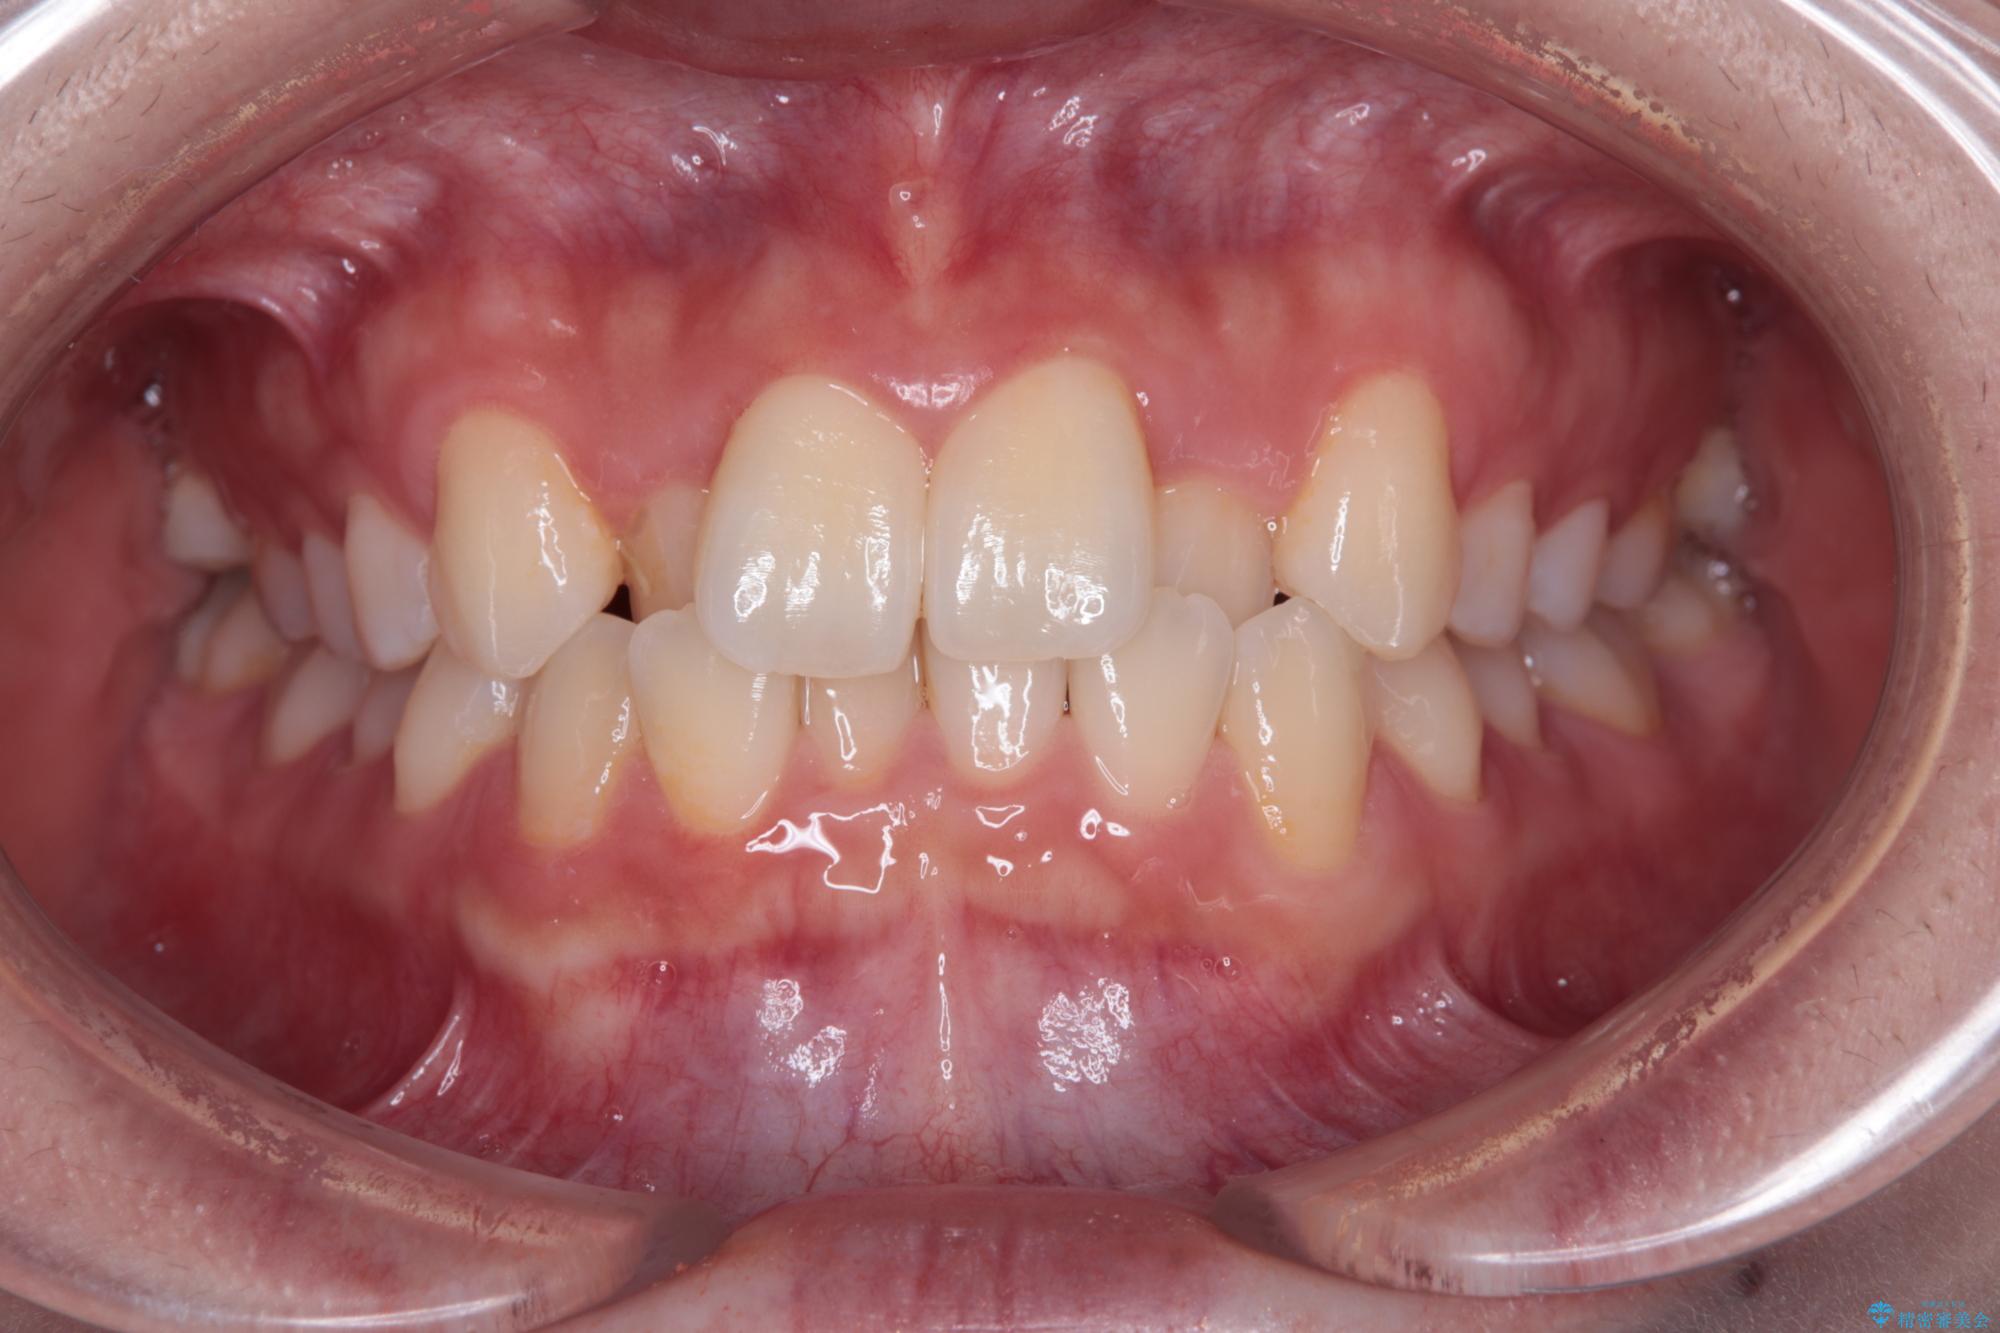

- 上顎前歯のクロスバイトを気にして来院された患者様です。

ワイヤー矯正でもマウスピース矯正でも対応可能でしたが、マウスピースによる自己管理に一切の自信がないとのことで、ワイヤー装置にて矯正治療を行うこととしました。

装置の外見を気にしていましたが、短期間で治療を終えることができるだろうと伝えると、安価であるメタルブラケットを選択されました。

想定通り、1年強で綺麗に仕上げることができました。